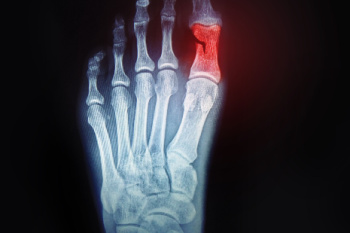

Gout is a painful condition that frequently affects the feet, especially the big toe joint, where sharp uric acid crystals can form and irritate the joint. This buildup leads to sudden flares of intense pain, swelling, redness, and warmth that make standing or walking very difficult. Flares can last for days or weeks and tend to return over time, sometimes spreading to the ankle or other joints in the foot. If untreated, repeated attacks can cause lasting damage and lead to the formation of tophi, which are hard lumps under the skin that restrict movement and deform the joint. Risk factors that raise the chance of developing gout include obesity, use of diuretics, diets high in red meat, shellfish, or sugary drinks, in addition to chronic conditions like high blood pressure, diabetes, or poor kidney function. A podiatrist can diagnose gout in the feet and provide treatment to reduce pain and protect joint health. If you have symptoms of gout, it is suggested that you schedule an appointment with a podiatrist for effective relief and prevention tips.

Gout is a type of arthritis caused by a buildup of uric acid in the bloodstream. It often develops in the foot, especially the big toe area, although it can manifest in other parts of the body as well. Gout can make walking and standing very painful and is especially common in diabetics and the obese.

Gout can easily be identified by redness and inflammation of the big toe and the surrounding areas of the foot. Other symptoms include extreme fatigue, joint pain, and running high fevers. Sometimes corticosteroid drugs can be prescribed to treat gout, but the best way to combat this disease is to get more exercise and eat a better diet.